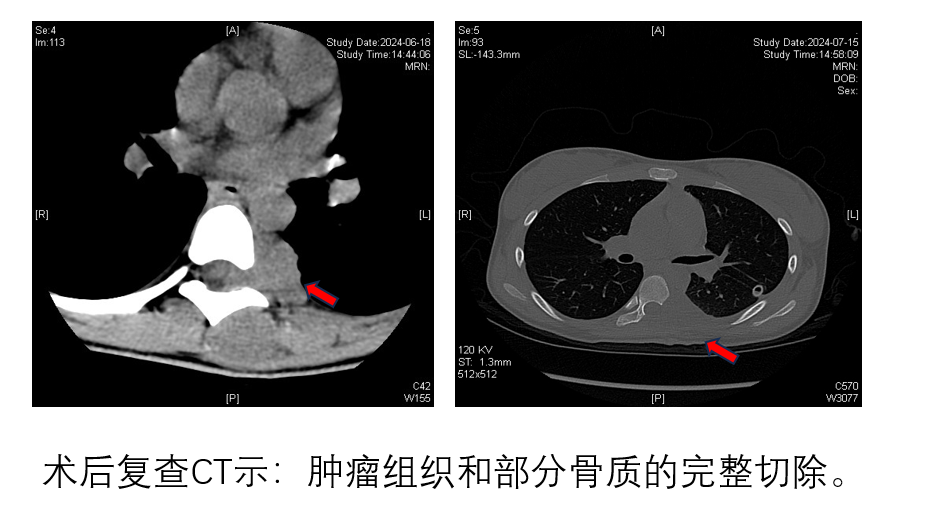

经过精心的术前准备,多学科接力手术正式开始。唐仪副主任医师精准完成2根肿瘤滋养动脉的栓塞,林兴主任医师在胸腔镜下分离肿瘤组织和主动脉,不到1小时就完成肿瘤前方的分离。骨科与运动医学中心徐杨主任医师和黄江湖副主任医师按照术前计划,在脊髓神经电生理监测下,完整切除了肿瘤及包裹的T7、T8左侧椎弓根、椎板和椎体附件、肋骨和壁胸膜,全过程未暴露肿瘤组织,保证了肿瘤切除的安全边界。术后患者脊髓神经功能完全正常,在术后3天即在支具的保护下床活动,目前已完成第一次术后化疗。术后病理显示为腺泡状横纹肌肉瘤,增殖指标ki67 90%+。